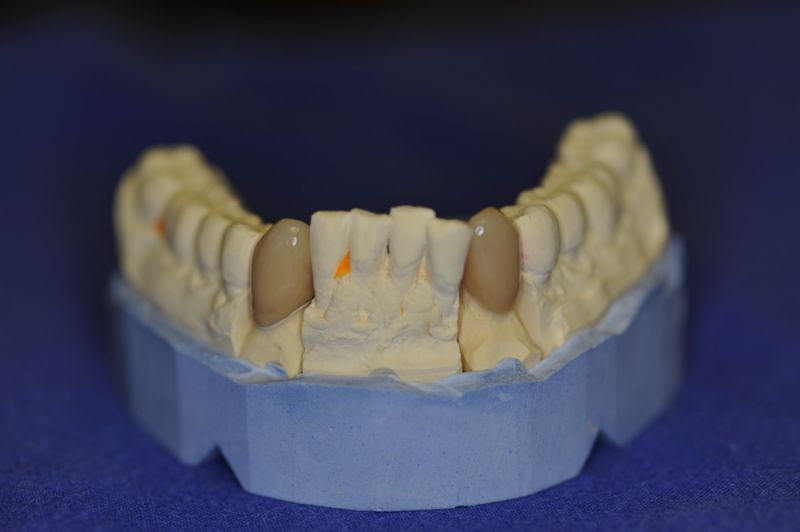

Der Patient erhält die beiden letzten Kronen zur Einstellung der dynamischen Okklusion.

In diesem Fall möglich über die Herstellung von zwei Eckzahnkronen